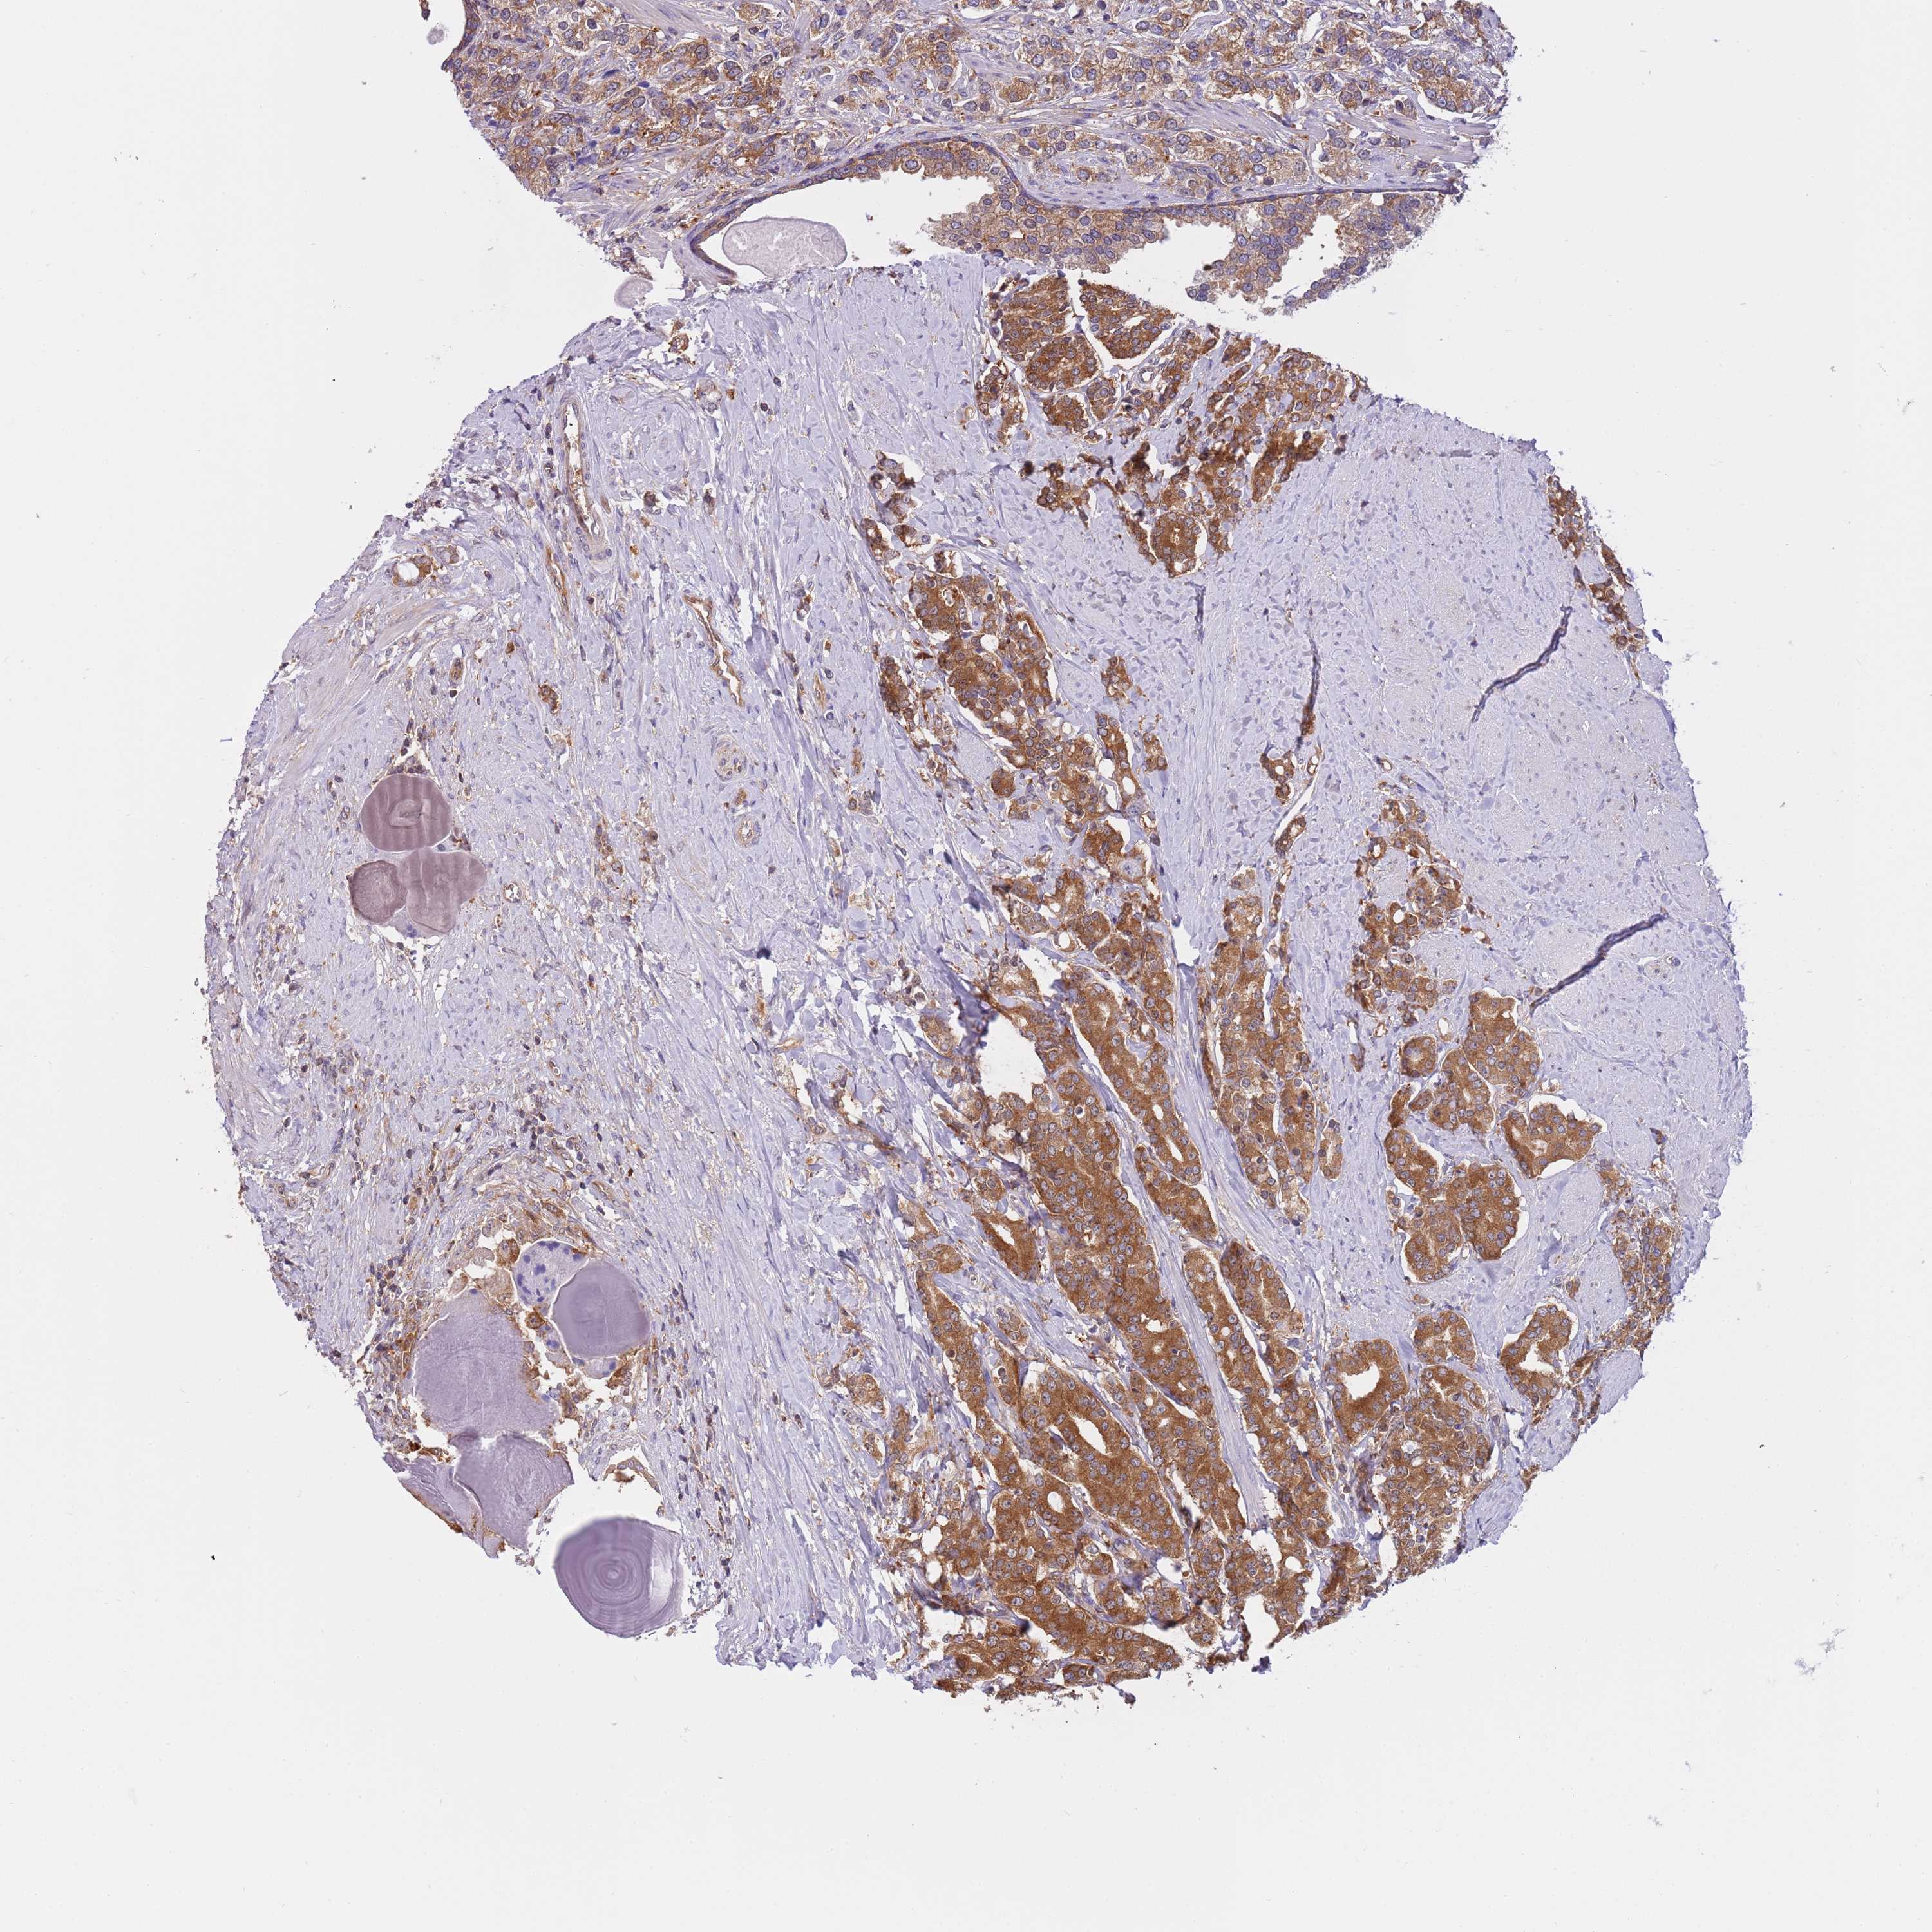

PROSTATE CANCER - Protein expressioni

A mouse-over function shows sample information and annotation data. Click on an image to view it in a full screen mode. Samples can be filtered based on level of antibody staining by selecting one or several of the following categories: high, medium, low and not detected. The assay and annotation is described here.

Antibody stainingi

Antibody staining in the annotated cell types in the current human tissue is reported as not detected, low, medium, or high, based on conventional immunohistochemistry profiling in selected tissues. This score is based on the combination of the staining intensity and fraction of stained cells.

Each image is clickable and will lead to virtual microscopy that enables deeper exploration of all samples and also displays staining intensity scores, fraction scores and subcellular localization as well as patient and tissue information for each sample.

Antibody HPA039291

Antibody HPA044062

Antibody CAB017448

Staining

High

Medium

Low

Not detected

Intensity

Strong

Moderate

Weak

Negative

Quantity

>75%

75%-25%

<25%

None

Location

Nuclear

Cytoplasmic/membranous

Cytoplasmic/membranous,nuclear

Adenocarcinoma, High grade